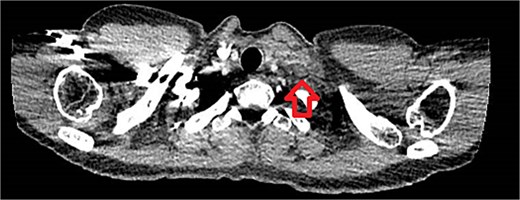

The patient presented to the emergency department the same day with shortness of breath. Investigations were normal except for a mildly elevated D-dimer. A CT pulmonary angiogram excluded pulmonary embolism but confirmed the supraclavicular mass (Fig. 5). The patient was reassured and referred back to the breast clinic.